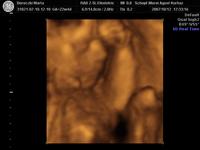

Nagyon édes a kisfiatok! És milyen helyes kis füle van!

Azért lehet látni jól az arcát, aranyos mikor ásít egy nagyot!